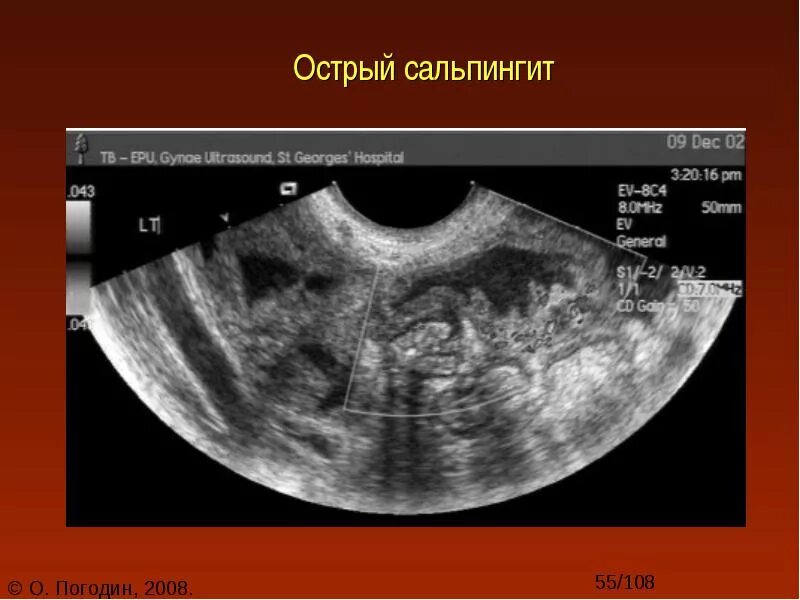

Сальпингит и оофорит что это